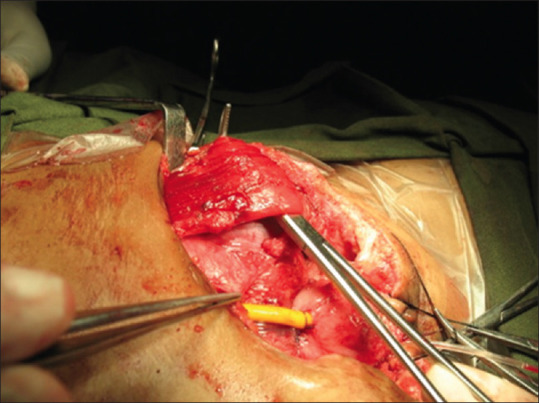

Background: Wound dehiscence is one of the main complications in complete primary repair of exstrophy (CPRE). In our pediatric urology unit, we have switched to the use of inferior epigastric artery based rectus abdominis flap cover for abdominal wall closure in addition to measures like osteotomy and postoperative hip spica.

Methods: This study was conducted from June 2014 to June 2021 comparing two groups of the patients; group I consisted of thirty patients of CPRE with rectus flap repair of abdominal wall (CPRE-RF) and group II consisted of thirty patients with CPRE without rectus flap. Clinical and surgical details, including the outcome with regards to wound dehiscence and continence, were recorded.